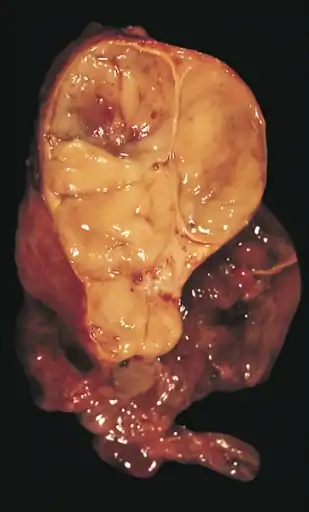

An encapsulated cystic thymoma.

A locally invasive circumscribed thymoma (mixed lymphocytic and epithelial, mixed polygonal and spindle).